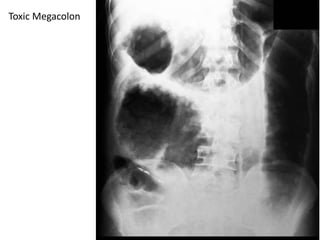

Plain Abdominal X-ray:

Thumbprinting appearance Thickening of the colonic wall + bowel

wall edema.

• Colonic segmental dilatation exceeding 5 cm with an irregular edge

outlined by gas, correlates strongly with ulceration.

• In toxic megacolon, the bowel is dilated with loss of haustral

markings.

Toxic Megacolon